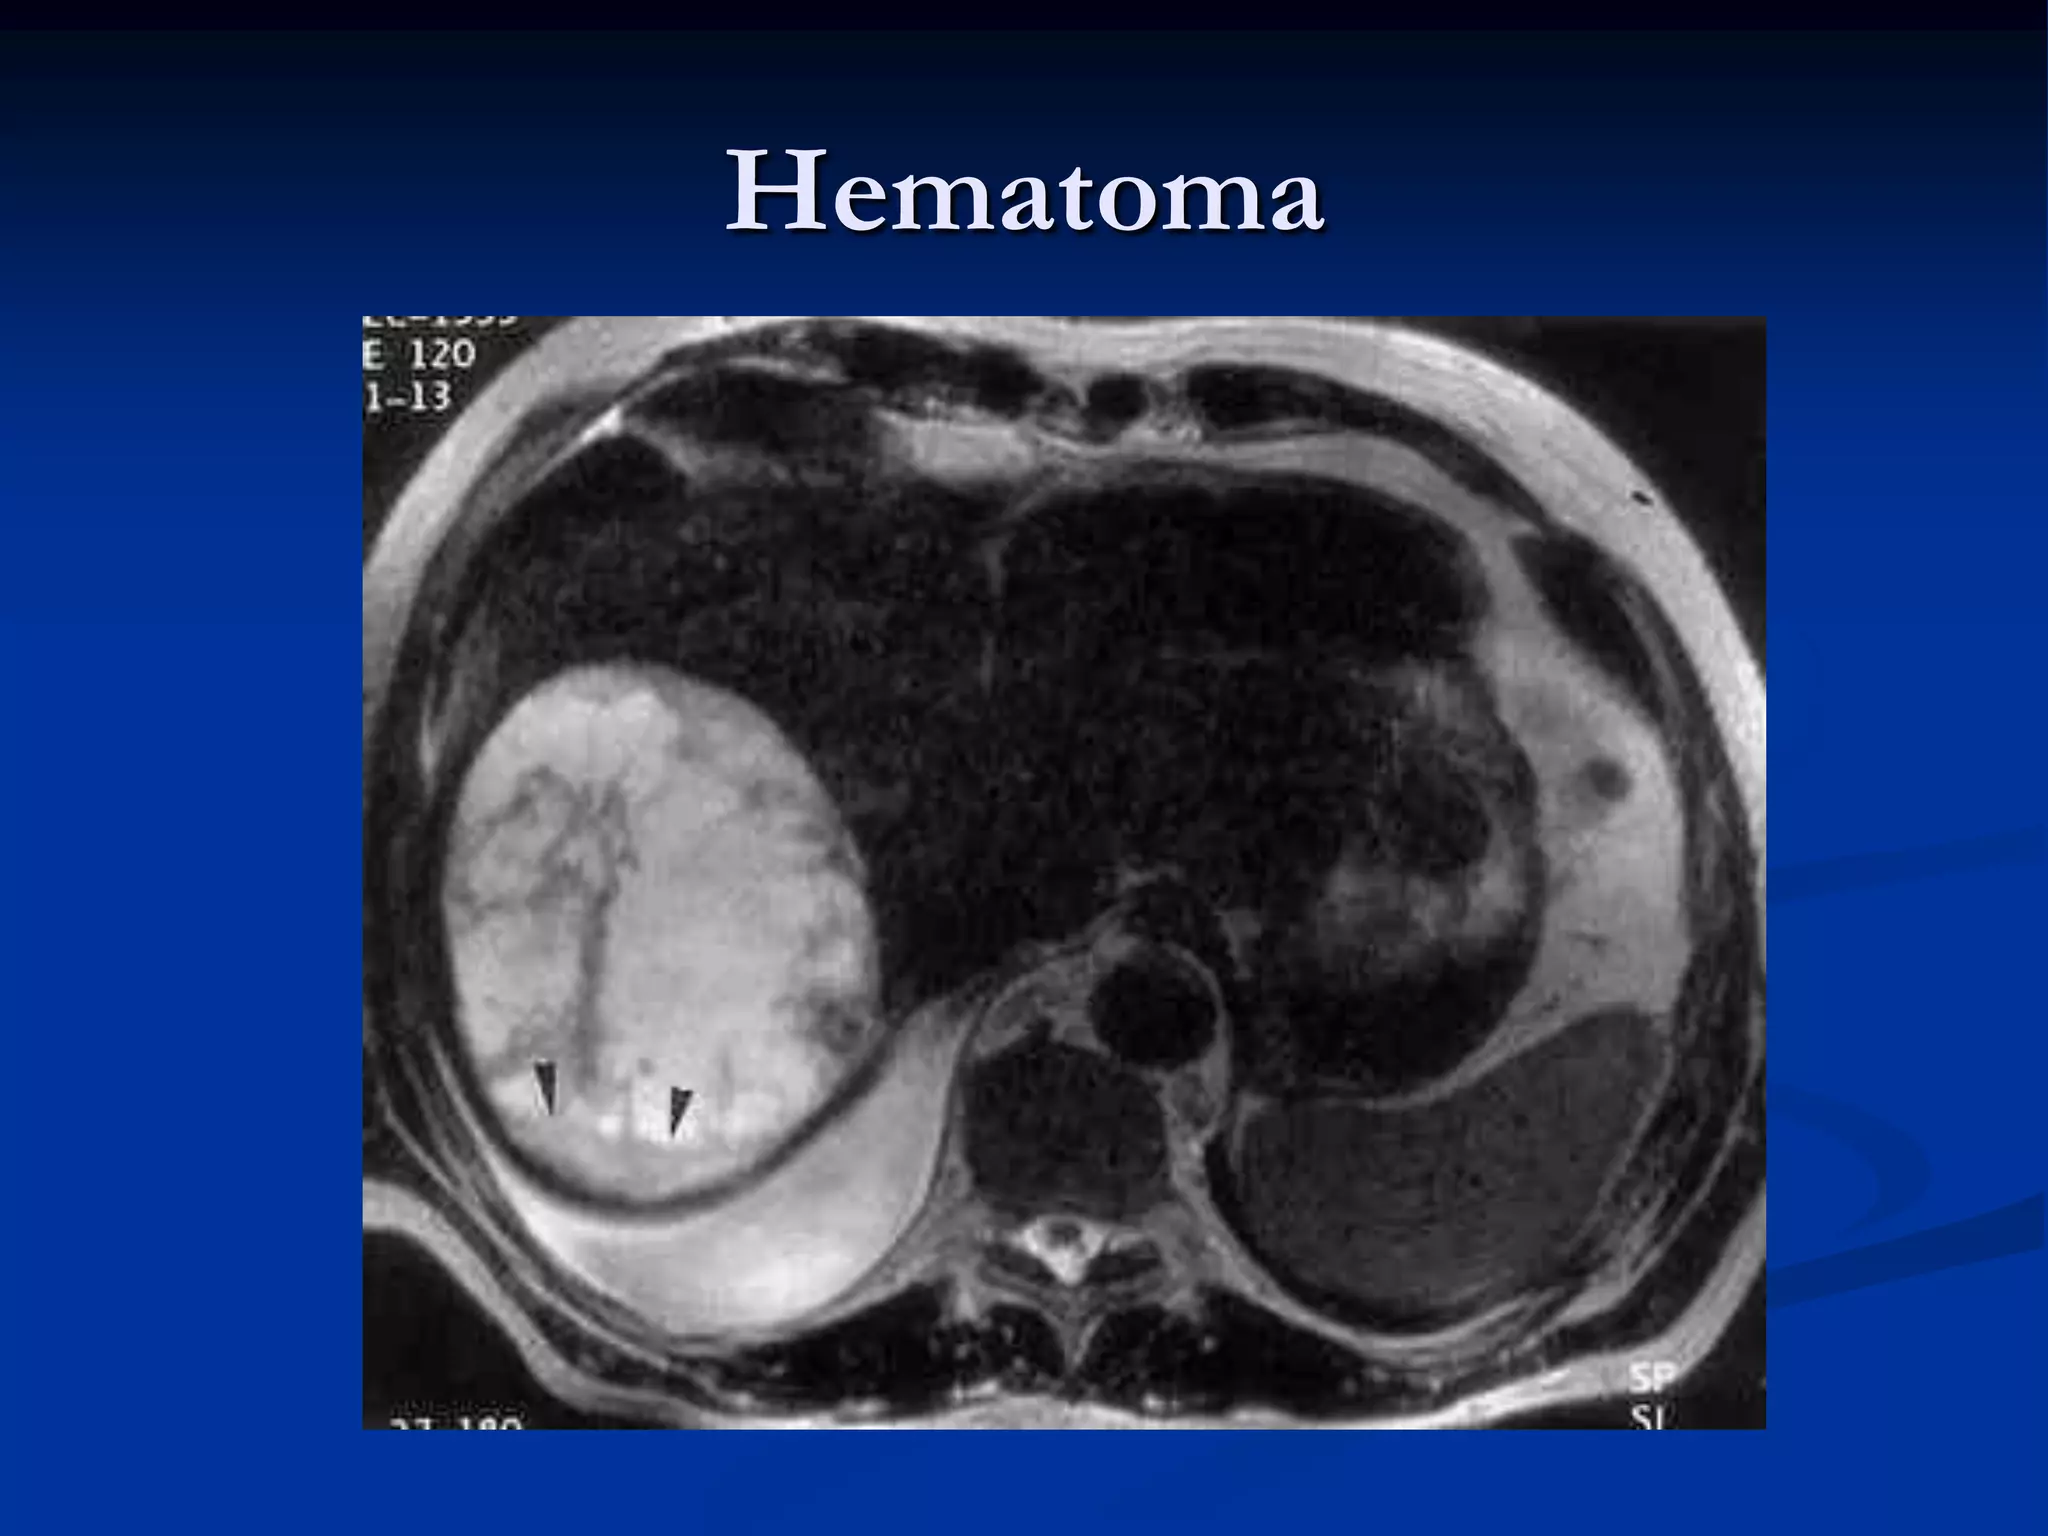

Hematoma

   En el cerebro un sangrado de cierto tiempo tiene un T2

corto porque sustancias de degradación de la sangre

(hemosiderina) produce heterogeneidades locales y

como consecuencia un desfase rápido de los

protones, poca señal que se ve oscura en la imagen

(hipointensa).

Imágenes potenciadas enT2 de los diferentes tejidos según su grado de relajación T2 en un momento determinado  En el cerebro un sangrado de cierto tiempo tiene un T2 corto porque sustancias de degradación de la sangre (hemosiderina) produce heterogeneidades locales y como consecuencia un desfase rápido de los protones, poca señal que se ve oscura en la imagen (hipointensa).